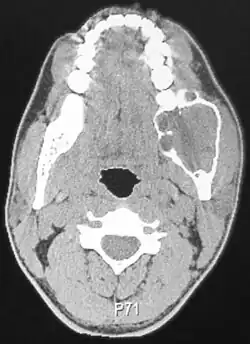

Ameloblastomas can be found both in the maxilla and mandible. Although, 80% are situated in the mandible with the posterior ramus area being the most frequent site.[9] The neoplasms are often associated with the presence of unerupted teeth, displacement of adjacent teeth and resorption of roots.[10]

Radiographically, the tumour area appears as a rounded and well-defined lucency in the bone with varying size and features. Numerous cyst-like radiolucent areas can be seen in larger tumours (multi-locular) giving a characteristic "soap bubble" appearance. A single radiolucent area can be seen in smaller tumours (unilocular).[8] The radiodensity of an ameloblastoma is about 30 Hounsfield units, which is about the same as keratocystic odontogenic tumours. However, ameloblastomas show more bone expansion and seldom show high density areas.[14]

Lingual plate expansion is helpful in diagnosing ameloblastoma as cysts rarely do this. Resorption of roots of involved teeth can be seen in some cases, but is not unique to ameloblastoma.[10]